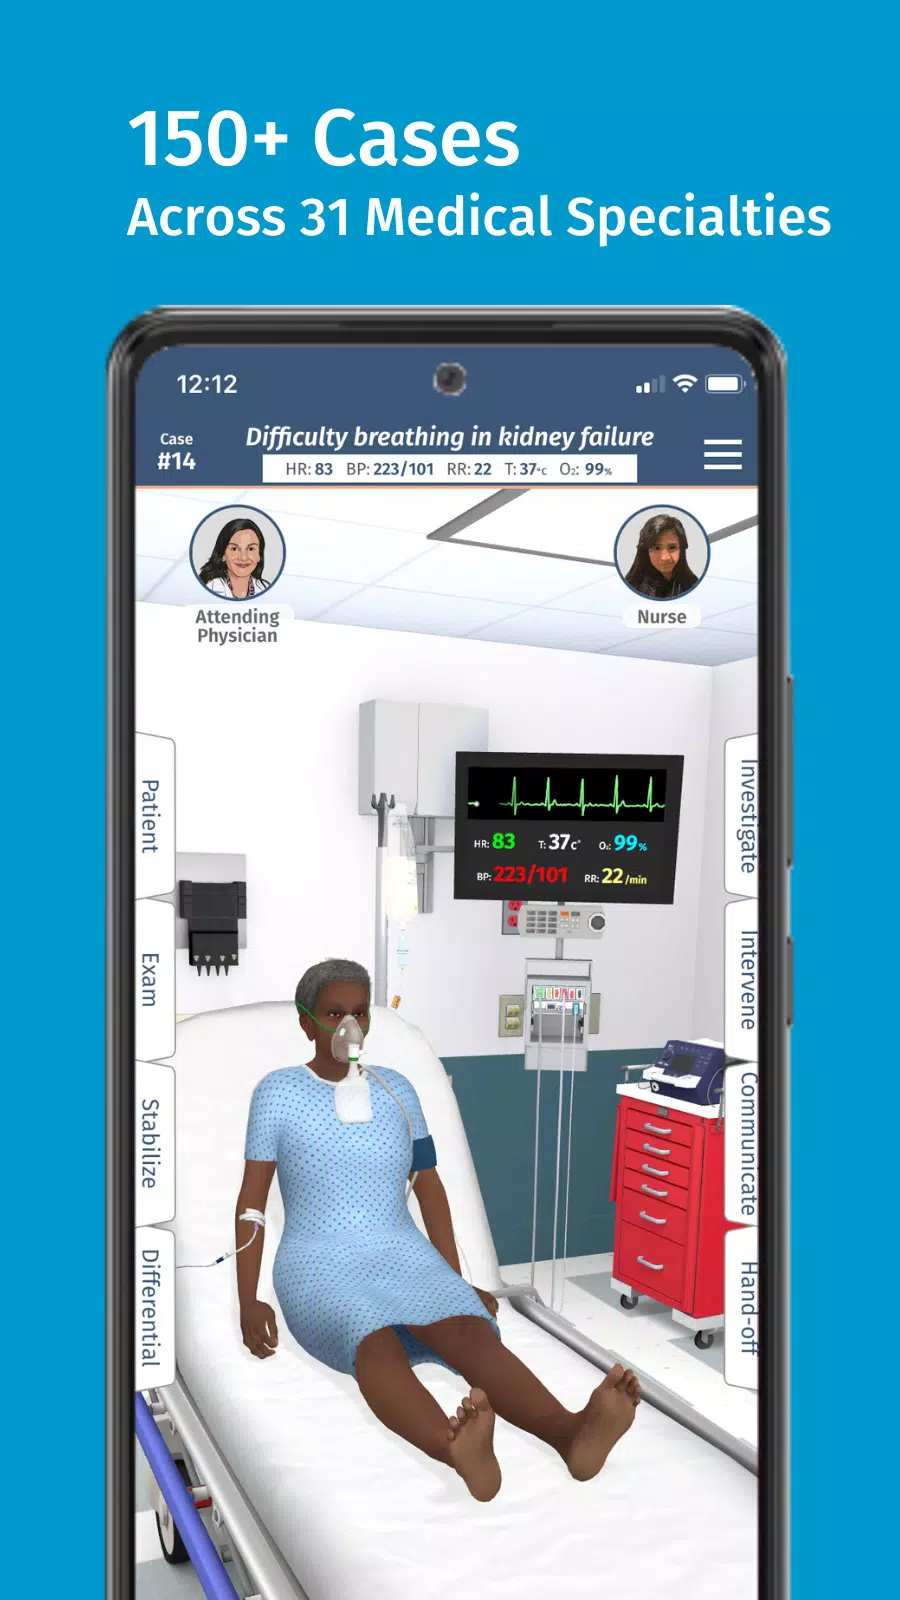

သင်သည်သင်၏အလုပ်များသောအချိန်ဇယားနှင့်ကိုက်ညီသောစွဲမက်ဖွယ်ကောင်းသောဆေးဘက်ဆိုင်ရာလေ့ကျင့်မှုများကိုရှာဖွေနေပါသလား။ အပြည့်အဝကုဒ်များထက်မကြည့်ပါနှင့်။ ဆေးဘက်ဆိုင်ရာသင်ယူသူများအတွက်ဒီဇိုင်း - အစွန်း virtual virtual simulation platform ။ ဘယ်နေရာမှာမဆို, ဘယ်နေရာမှာမဆို, ဘယ်နေရာမှာမဆိုအပြည့်အဝကုဒ်သည်လက်တွေ့ကျသော, သင်သည်သင်၏ပထမဆုံးဆေးကျောင်း၏ပထမနှစ်ကိုသွားလာသည်ဖြစ်စေ Residency အတွက်ပြင်ဆင်ခြင်းသို့မဟုတ်သင်၏လက်ရှိကျွမ်းကျင်မှုများကိုမြှင့်တင်ရန်ရှာဖွေခြင်း,

ကုဒ်အပြည့်အဝ code ၏တောင်းဆိုခြင်းခြင်း simulation လေ့ကျင့်ရေးလေ့ကျင့်ရေးနှင့်အတူရှုပ်ထွေးသောဆေးဘက်ဆိုင်ရာကိစ္စရပ်များလေ့ကျင့်နိုင်ပြီးသင့်အားအခိုက်အတန့်ရှိသည့်အခါတိုင်းသင်၏ဆေးခန်းကျွမ်းကျင်မှုများကို Hone နိုင်သည်။ မိုဘိုင်းထုတ်ကုန်များအတွက်ဒီဇိုင်းရေးဆွဲထားသည့်ကုဒ်အပြည့်အ 0 သည်သင်ပိုင်ဆိုင်ပြီးသောကိရိယာများကို အသုံးပြု. သွားလာရန်နှင့်တိုးတက်ရန်ခွင့်ပြုသည်။

အမေရိကန်ဆေးရုံများကို ဦး ဆောင်ခြင်းနှင့်လိုင်စင်ရပညာရှင်များ၏တင်းကြပ်စွာပြန်လည်သုံးသပ်ခြင်းမှဆေးကုသမှုဆိုင်ရာပညာရှင်များကတီထွင်ခြင်းဖြင့်တီထွင်ထုတ်လုပ်နိုင်ပြီး Code ၏ Simulats သည်စက်မှုလုပ်ငန်းဆိုင်ရာအကောင်းဆုံးအလေ့အကျင့်များကိုလိုက်နာသည်။ ၎င်းသည်ကျွန်ုပ်တို့၏ကမ္ဘာလုံးဆိုင်ရာသင်ယူသူအသိုင်းအဝိုင်းအတွက်အရည်အသွေးမြင့်သင်ယူမှုအတွေ့အကြုံကိုသေချာစေသည်။

အပြည့်အဝကုဒ်အကန့်အသတ်မဲ့ထပ်ခါတလဲလဲဖြစ်ရပ်များသည်သင့်အားရောဂါရှာဖွေခြင်းနှင့်စီမံခန့်ခွဲမှုနှစ်ခုလုံးကိုလက်တွေ့ကျင့်သုံးရန်ခွင့်ပြုသည်။ ၎င်းသည်သင့်အားရှုပ်ထွေးသောအစစ်အမှန်ကမ္ဘာကြီးကိုယုံကြည်မှုတိုးများလာစေရန်သင့်အားပြင်ဆင်သည်။

accme မှတစ်ဆင့်အသိအမှတ်ပြုထားသော Code ၏ပြောင်းလွယ်ပြင်လွယ်ခြင်းနှင့်ထိတွေ့ခြင်းခြင်းဆိုင်ရာခြင်းမျိုးခြင်းဆိုင်ရာဆိုးရွားသောစိန်ခေါ်မှုများကိုအပြည့်အ 0 ယူထားသော, ကျွန်ုပ်တို့၏ Pro + cme subscription နှင့်အတူ CME ခရက်ဒစ် 90 အထိရနိုင်သည်။ ယနေ့သင်၏ခရီးကိုယနေ့အပြည့်အဝကုဒ် Pro + cme ဖြင့်စတင်ပါ။